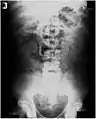

Vibrator stuck in the rectum can be seen on this abdominal X-ray.